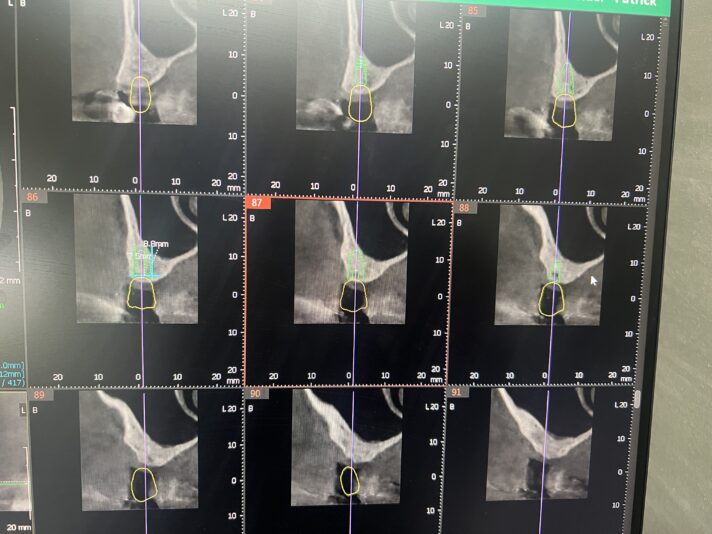

I recently placed an implant that I’m worried about the prognosis. My previous cases have all been free handed. I had my lab make a guide for this case. I ended up relying too much on the guide and placed the implant too close to the adjacent tooth (0.8mm). Has anyone else placed one this close and had it fail or be successfull? Im…

Anecdotally, I have at times, and many others have placed implants closer than we wish we would have to adjacent teeth. It’s happened once or twice. And aside for a few sleepless nights, I (and the patient) have had zero issues from it.<br…